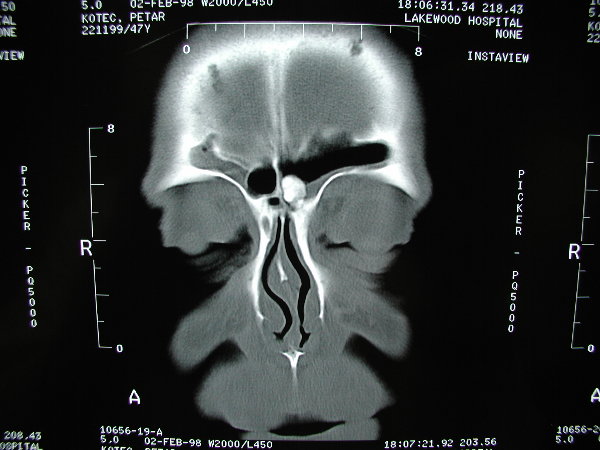

The patient above had two separate osteomas within his sinuses.  On the right it is within the frontal sinus outflow tract, and on the left it is within the frontal sinus iteslf.  The osteoma on the right was very symptomatic, causing obstruction and severe pain, while the left was asymptomatic.  The right was removed endoscopically, and the left is being observed for the time being.

An osteoma is a benign boney growth that can grow and occlude paranasal sinuses and cause problems.